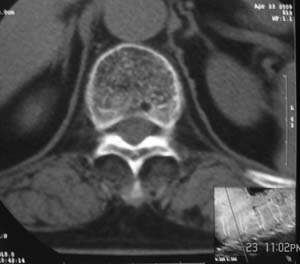

患者,女,72岁,胸背部疼痛3月余,无明显外伤史。曾应用局部封闭、非甾体类止痛药治疗效果不明显,近来疼痛缓解频感背困,平卧缓解,近日行ct检查发现胸12椎体病变,烦请同道发表意见,诊断什么?有何治疗经验!谢谢!!!

标绘图示:第十二胸椎级第一腰椎椎体楔形改变。ct扫描示:第十二胸椎椎体骨质结构紊乱,并可见一囊状低密度影,边缘可见硬化,椎体皮质完整。

考虑:第十二胸椎陈旧性骨折、许莫氏结节。